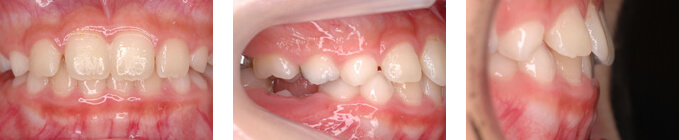

叢生(そうせい)と顎の右方偏位 O様

| 年齢 | 10歳女性 |

|---|---|

| 治療期間と通院回数 | 2年3か月/27回 |

| 治療費総額 | 35.5万円 |

| 主訴 | 前歯の凸凹 |

| 診断名 | 上顎前歯部叢生及び下顎の右方偏位 |

| 主な治療装置 | セクショナルアーチ エクスパンジョンプレート |

| 抜歯部位 | 非抜歯 |

| リスクについて | 下顎骨の歪みは早めに治療することで改善することが見込めますが、原因を取り除いても既に歪みが骨格に及んでいる場合は完全に治しきれないことがあります。 |

治療前

治療後

この症例の解説

歯の生え替わりのときに永久歯の位置が悪かったために下顎が大きく右にずれ、さらに歯列まで非対称になってしまった症例です。

悪い位置に生えてきた永久歯の位置を治したあと、就寝時に装着する装置で下顎を正しい位置に誘導しました。

1年3ヶ月で大きく改善しました。